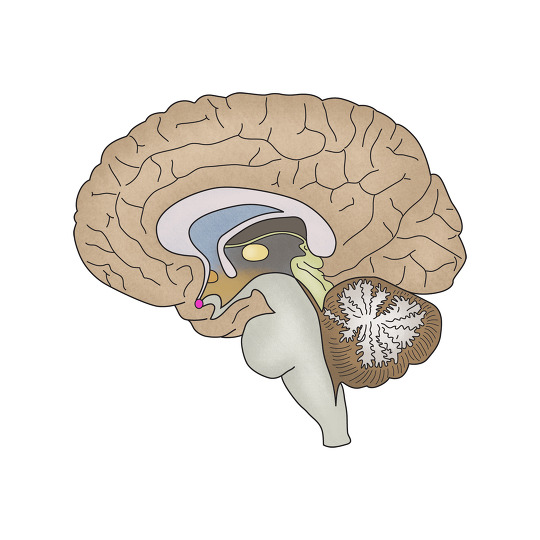

뇌신경 전달물질의 불균형으로 인한 사고, 감정, 행동의 이상으로초래되는 정신질환 및 증상을 진단, 치료하는 과입니다.